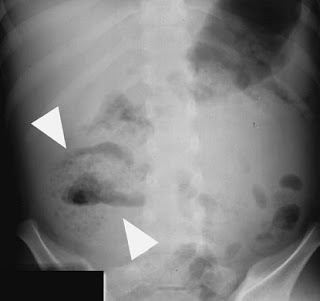

Ruptured Appedicitis in abdominal X-ray

Ruptured appendicitis (arrow heads).

Note the presence of an ill-defined mottled gas pattern within the RIF,with an air–fluid level, caused by the ruptured appendix.

Role of Abdominal X-ray in Appendicitis

Radiological features in abdominal X-ray:

• Abdominal X-ray Is neither sensitive nor specific for Appendicitis but can provide clues.

• The presence of a calcified appendicolith in the RLQ ,combined with

abdominal pain,has ahigh positive predictive value for acute appendicitis.

• Other signs are less specific and include caecal wall thickening,small-bowel ileus and decreased small-bowel gas in the RIF.

• Free peritoneal fluid can lead to loss of the psoas out line,loss of the fat planes around the bladder and loss of definition of the inferior liver outline.